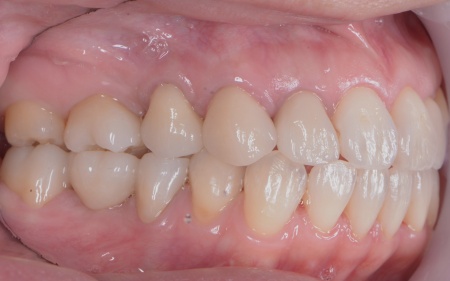

40代女性 矯正治療で噛み合わせを整えたあとセラミックの被せ物・詰め物で修復した症例

まずは矯正治療を優先し、噛み合わせが整ってから虫歯の再発リスクの低いセラミックの被せ物・詰め物などで歯の形態と機能を回復する方針を提案し、同意いただきました。

なお、左上の奥歯には人工歯根を埋め込んで失った歯を補うインプラントが装着されていたものの、人工歯根の位置や骨との結合状態に問題はありませんでした。

そのため、人工歯根部分はそのまま活用し上部に装着する人工歯のみを新しく作製しています。

最後に噛み合わせ全体のバランスを確認しながら新しく作製した被せ物や詰め物を装着し、見た目に問題がないか、噛み合わせが安定しているかを確認し、治療を終了しました。